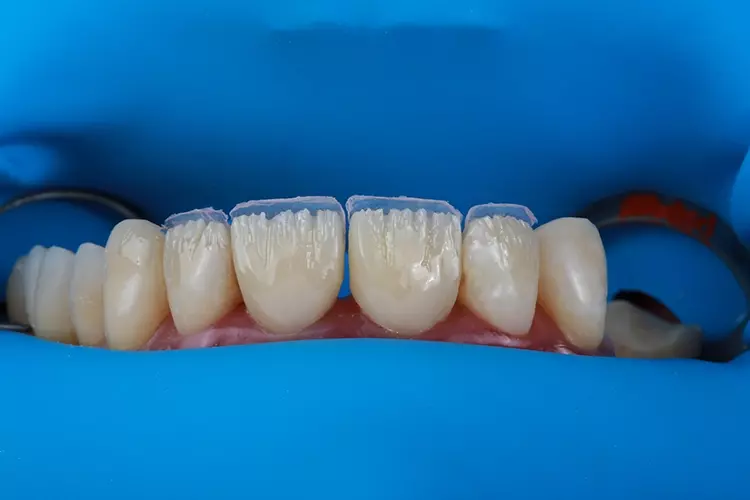

Das für das Mock-up verwendete Material bestand aus selbsthärtendem Mikro-Hybrid-Komposit für provisorische Kronen und Brücken (Structur 2, VOCO). Das thermoviskose VisCalor bulk (VOCO) wurde additiv in einen weiteren Silikonschlüssel injiziert, um die okklusalen Aspekte zahlreicher OK-Zähne sowie der rechten unteren Prämolaren und Molaren des Unterkiefers direkt im Mund zu rekonstruieren. Die Eckzahnführung wurde hingegen mit Admira Fusion (VOCO) wiederhergestellt.

Die Kronen für 11 und 21 wurden mit einer 5-Achs-Fräs- und Schleifmaschine (inLab MC X5; Dentsply Sirona) aus einer nanokeramischen Komposit CAD/CAM-Ronde (Grandio disc, A1, VOCO) gefräst und mit Bifix Hybrid Abutment (VOCO) auf einem Abutment aus Metall (Grand Morse, Neodent Titanium Base Neodent, Straumann) im Labor zementiert. Die Kronen wurden in ihrer endgültigen Position eingegliedert (Abb. 18). Jede Krone wurde mit direkten Komposit-Veneers modifiziert.

Letztendlich hängt der Behandlungserfolg weniger von der Erfahrung der Behandelnden als vielmehr von der Beachtung und Einhaltung der Planungs- und Ausführungsprotokolle bei der Anwendung der Technik ab. Eine direkte Schichtung von Komposit-Veneers ist preisgünstiger als herkömmliche keramische Veneers und kann in nur einer Behandlungssitzung durchgeführt werden.